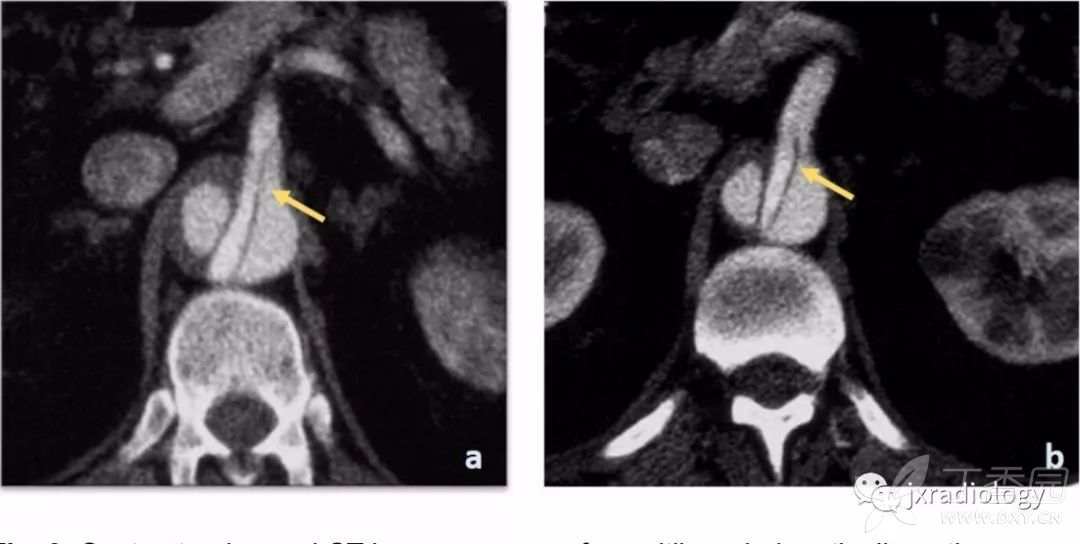

图3:对比增强CT显示内膜瓣延伸至肠系膜上动脉的起始部,导致静态性阻塞。

主动脉夹层的一个重要的并发症是分支阻塞,可以是静态的或动态的。在第一种静态阻塞机制中,内膜瓣进入分支血管起始部而没有再延伸( 图3 )。这导致这个分支的压力上升和血栓形成,引起局部血管狭窄及器官缺血。

动态阻塞是指当撕裂内膜像窗帘一样覆盖主动脉的一个分支;也可导致局部缺血( 图4 )。

图4:A型主动脉夹层患者的对比增强CT。

在矢状MIP(a)中,可见真腔位于前面,假腔占据大部分主动脉直径。内膜钙化有助于识别真腔。从真腔(a图和c图)看来,即使腹腔干起源于真腔,假腔的压力增加会导致内膜向前移位,压迫真腔并阻塞腹腔干的开口(c图)。肠系膜上动脉(a图)的开口处可见相同的机制。

可见两个假腔,内膜瓣延伸至腹腔干(a图箭头所指)和肠系膜上动脉(b图箭头所指)。